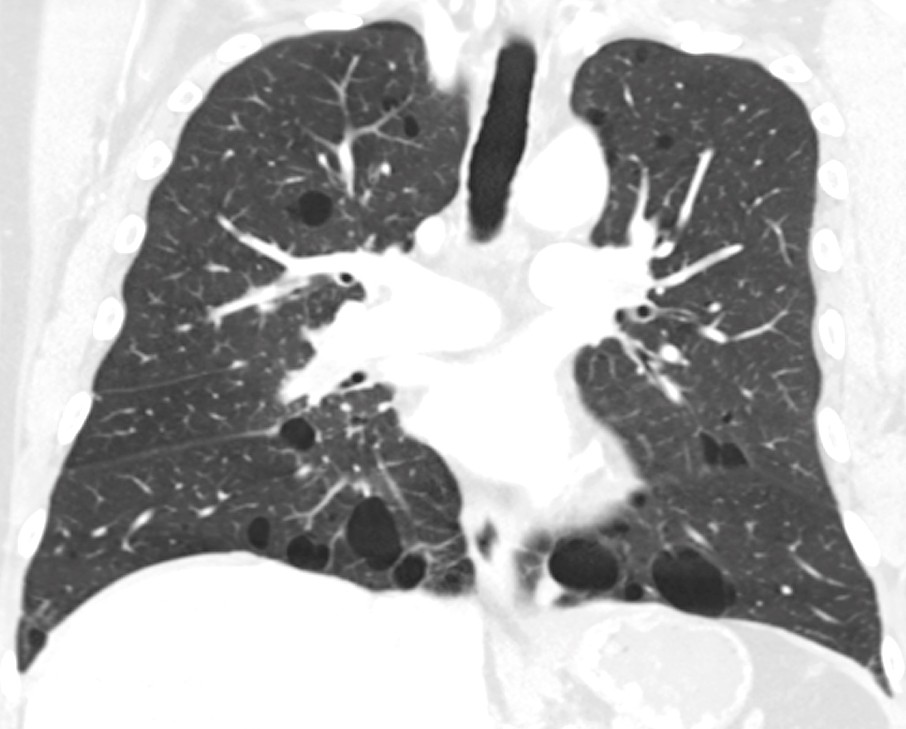

Lungemedisinsk utredning inkluderer CT thorax lavdose og vurdering av lungefunksjonen med spirometri, gassdiffusjonstest og oksymetri. Funn av typiske lungecyster, eventuelt med pneumothorax, er ofte det som leder til diagnosen. Lungecyster oppstår hos ca. 90 % av pasientene med Birt-Hogg-Dubé-syndrom, vanligvis etter 20 års alder. Lungecyster er hulrom med en definert vegg som er < 2 mm tykk (8). Pasientene har oftest bare noen få, men enkelte kan ha flere hundre cyster (9). De fleste cystene er < 2 cm i diameter, men kan bli betydelig større og ha protruerende venuler og intracystiske septa. Cystene finnes oftest i midtre og nedre lungefelt og har subpleural og peribronkovaskulær beliggenhet (figur 1).

Det er fravær av fibrose, lungefortetninger, inflammasjon og glandelpatologi. Innsiden av cystene er kledd av pneumocytter (10), og histologisk kan de ligne emfysem. Patogenesen for cystedannelsen er ukjent. Tabell 1 viser thoraxradiologiske karakteristika ved Birt-Hogg-Dubé-syndrom og de viktigste differensialdiagnosene (11).